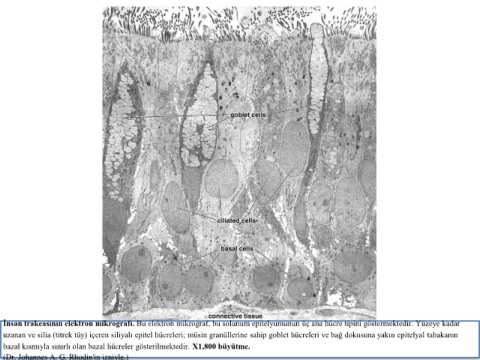

İnsan trakeasının elektron mikrografı. Bu elektron mikrograf, bu solunum epitelyumunun üç ana hücre tipini göstermektedir. Yüzeye kadar

uzanan ve silia (titrek tüy) içeren siliyalı epitel hücreleri; müsin granüllerine sahip goblet hücreleri ve bağ dokusuna yakın epitelyal tabakanın

bazal kısmıyla sınırlı olan bazal hücreler gösterilmektedir. X1,800 büyütme.

(Dr. Johannes A. G. Rhodin'in izniyle.)